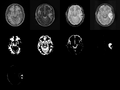

We're working on the supervised segmentation and atlas optimization of longitudinal TBI data.

On anatomical MRI scans, to quantitatively analyze the cortical thickness, white matter changes, we need to have a good segmentation on TBI images. However, for TBI data, standard automated image analysis methods are not robust with respect to the TBI-related changes in image contrast, changes in brain shape, cranial fractures, white matter fiber alterations, and other signatures of head injury.

• We applied the preliminary algorithm to current data and fixed some bugs in the code.

• Our collaborators helped us to validate our current results of supervised segmentation. We got some comments and feedback from our collaborators, which are very important for us to improve the current algorithm.